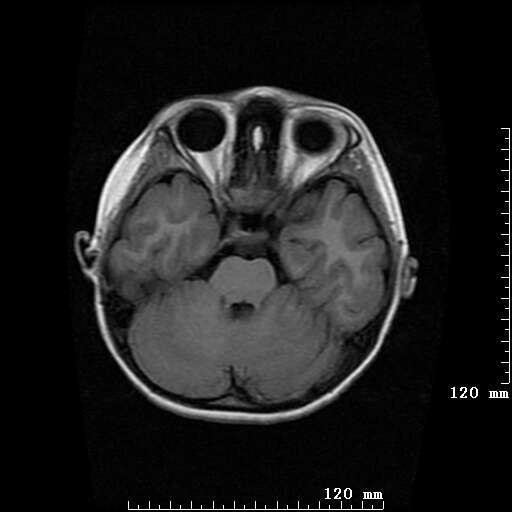

女,7岁,三岁才说话、走路。现智力尚可,走路不稳。临床怀疑大脑发育不全。

考虑 脑白质发育不良

脑折质变薄,双侧侧脑室稍扩张,支持考虑脑折质发育不良

侧脑室周围白质软化症。

考虑胼胝体发育不全,髓鞘形成不良。

支持考虑胼胝体发育不全,髓鞘形成不良。

脑裂畸形伴灰质异位

侧脑室周围白质数量减少,侧脑室不对称性扩大,左侧侧脑室后角呈方形改变,脑沟加深,结合临床考虑脑室周围白质软化症(pvl)。期待结果!

只看出灰质异位

支持脑白质发育不良。